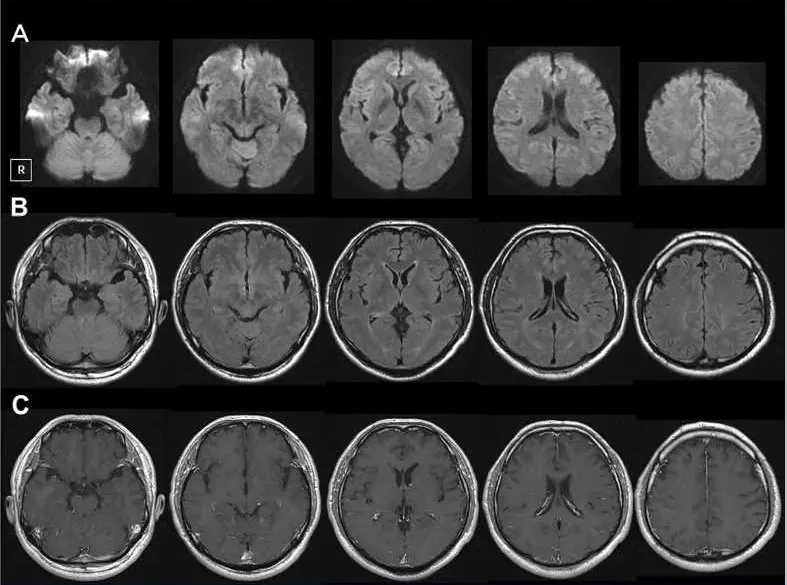

入院时,使用钆对比剂的脑部磁共振成像未显示异常(图1)。脑脊液(CSF)分析显示细胞计数为20/μl,蛋白质166 mg/dl,葡萄糖73 mg/dl。脑脊液中的白介素6(IL-6)水平升高至82.9 pg/ml(正常水平<8.7 pg/ml[3])。脑脊液的细菌培养、单纯疱疹病毒1+2和巨细胞病毒的聚合酶链反应呈阴性。副肿瘤性神经综合征的血清抗体(包括抗-Hu抗体)检测结果为阴性。因此,以上诊断排除了转移性脑肿瘤、细菌性脑膜炎、单纯疱疹脑炎和副肿瘤性神经综合征。

图1. 入院时的脑磁共振成像,以下没有异常发现:(a)弥散加权成像,(b)流体衰减反转恢复,(c)钆对比剂增强T1加权成像